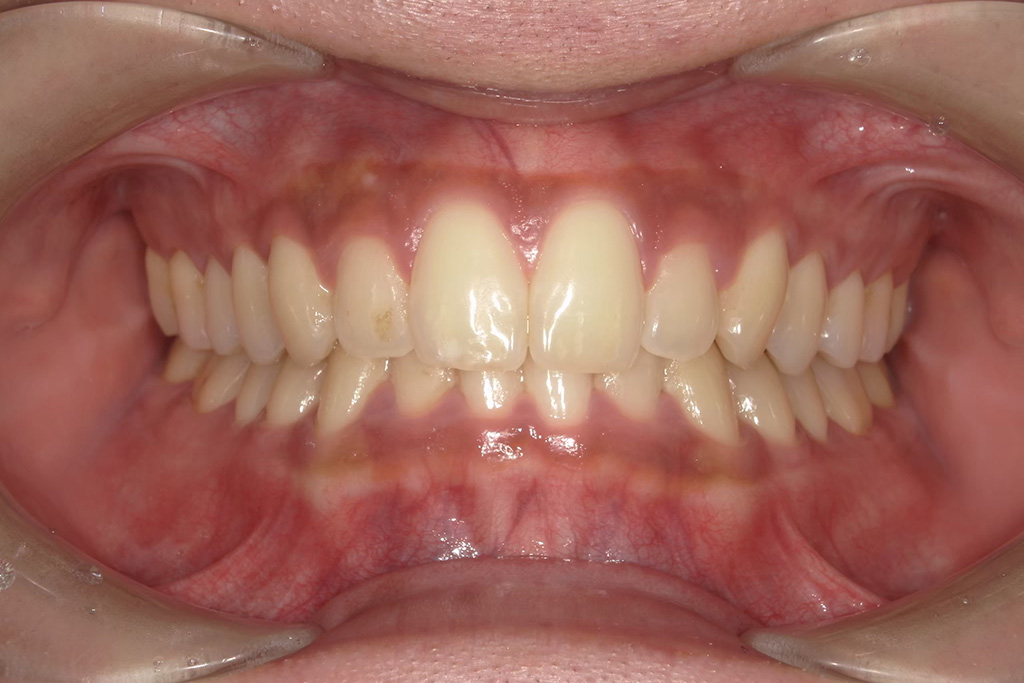

【2ヶ月後】ほぼ毎日フロスしたら…

2ヶ月後、ほぼ毎日フロスを続けた結果を比較してみたのがこちら。

● 歯ぐきの変化

● 清掃状態

● 本人の感想

「フロスするとき、40センチで全顎するのが難しい」

「奥歯が難しい」

「いっぱい取れた時たのしい」

「お肉食べた日すごい取れる」

とのことでした!